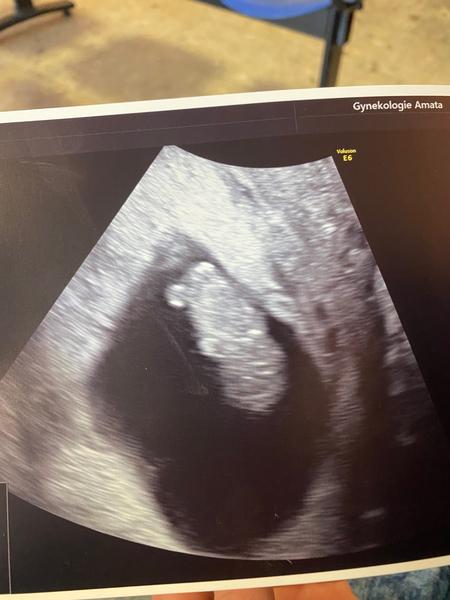

Děvčata tak v 10 hod. 🙏❤️